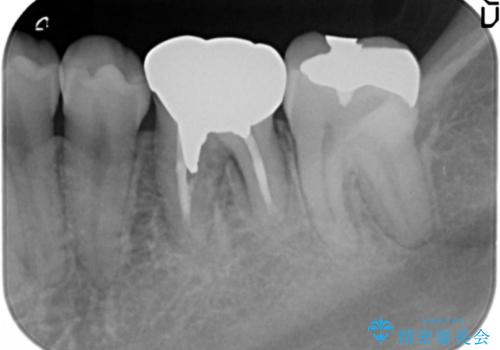

左下7番には、矯正治療前に虫歯をとり、CRで充填していました。

ただし、元のインレーが遠心マージンが縁下だったため、矯正治療後に歯ぐきの厚みを減らして、しっかり歯ぐきの上にマージンラインが来るように整える手術(ディスタルウェッジ)を行いました。

手術後、きちんとマージンラインが歯肉の上に来た状態で、セラミックインレー修復を行いました。

レーザーや電気メスで分厚い歯肉を焼いても一時的で、やがてまた元のように歯ぐきが上まで増殖しますので、今回は骨の厚みも調整し、7番の遠心を出来るだけ下げました。